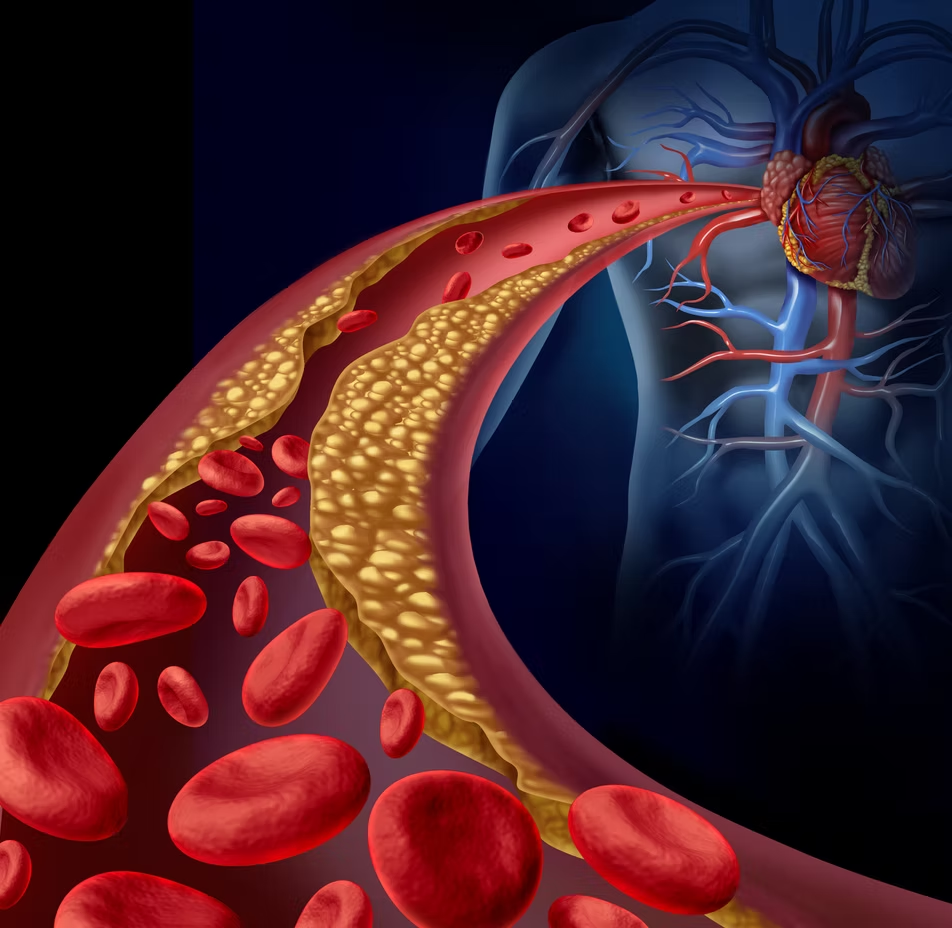

BOALA ARTERIALĂ CORONARIANĂ

Boala arterială coronariană este una dintre cele mai frecvent întâlnite boli de inimă. Nivelurile ridicate de colesterol, tensiunea arterială sau fumatul pot deteriora interiorul arterelor, ducând la o acumulare de plăci în interiorul pereților arteriali și împiedicând fluxul sangvin. Această situație indică începutul bolilor cardiace coronariene.

Cu cât se acumulează mai multă placă în arteră, cu atât artera devine mai îngustă, reducând și mai mult cantitatea de sânge care curge către inimă. Acest lucru diminuează cantitatea de oxigen care ajunge la inimă, provocând dureri în piept.

O arteră îngustă blocată în întregime de cheaguri de sânge duce la atac de cord (infarct miocardic). Lipsa sângelui bogat în oxigen duce la deteriorarea permanentă a mușchiului cardiac.